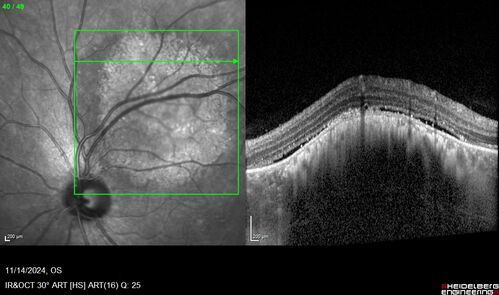

Small choroidal melanoma

28 year old man Serial images suggested that the lesion is growing

OD: sc20/16

OS: sc20/40+2

IOP: TP: OD:19 OS:16